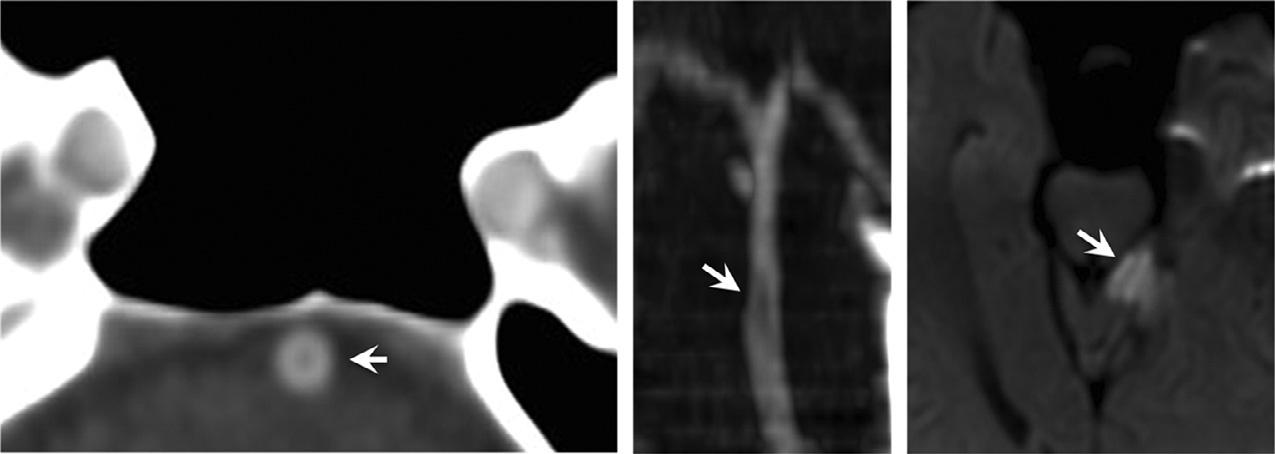

Fig.1.9. Coronalandsagittalreformattedimagescanmitigate volumeaveragingandstreakartifactsfromadjacentbony structures,improvingtheconspicuityofsubtlehemorrhage comparedtothatofthick-sliceaxialimagesalone.

WheninterpretingCTAimages,caremustalsobe takentonotconfusecertainimagingartifactscommonly seeninassociationwithdirectcatheterarteriography withCTAartifacts.Forexample,thedifferential diagnosisofcircumferentialirregularityofthecarotid arterywallinthesettingofbluntcarotidtraumaincludes carotidintimalinjury,fibromusculardysplasia,atheromatousdisease,orpotentiallyapoor-contrastbolus (Fig.1.10).Standingwavesthatarecausedbyvibrations fromhigh-pressurepowerinjectionofcontrastduring selectivecatheterarteriographyarenotincludedinthis differentialdiagnosis.

Fig.1.10. Subtleinternalcarotidintimalirregularity(arrows) causedbyblunttrauma,withbilateraldisplacedmandibular condylefractures(arrowheads).